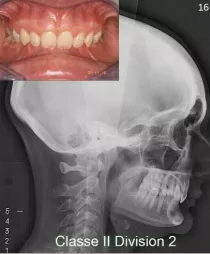

La mandibule est en retrait par rapport au maxillaire supérieur. Il peut s’agir d’un manque de développement de la mandibule et d’un maxillaire supérieur normal ou au contraire d’une mandibule normale et d’un maxillaire anormalement projeté vers l’avant. Parfois, les deux anomalies se conjurent associant un manque de développement de la mandibule et un maxillaire positionné trop en avant. Le profil facial classiquement observé est « convexe » ou « fuyant » tandis que l’on retrouve fréquemment une occlusion dentaire de classe II. L’appellation courante est le « rétrognathisme ».

Il existe de nombreuses variétés de Classe II squelettiques. Parmi les plus fréquentes, on distingue les Classe II squelettiques avec surplomb des incisives supérieures (Classes II Division 1) et les Classes II squelettiques avec recouvrement des incisives inférieures par les incisives supérieures (Classes II Division 2).

Classe II Squelettique Division 2 :

Classe II Squelettique Division 2